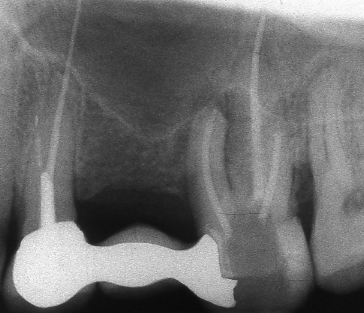

Оралната хирургия е дял от денталната медицина. Понятието орална хирургия е доста условно - с него се обозначават различни видове оперативни интервенции в областта на устната кухина, въпреки че дори и почистването на един кариес по своята същност представлява оперативна интервенция (некректомия); екстирпацията на един нерв от зъбен канал, почистването на зъбен камък, пиленето на зъб за корона и запълването на коренов канал също са оперативни интервенции, понякога технически доста сложни. Все пак всички тези манипулации са извън обема на оралната хирургия - тя включва екстракцията на ретинирани зъби, отстраняването на кисти от зъбен произход, на малки по обем доброкачествени тумори, и, разбира се, поставянето на зъбни импланти. Всички необходими манипулации за осъществяването на костна пластика при имплантатите също влизат в обема на оралната хирургия.